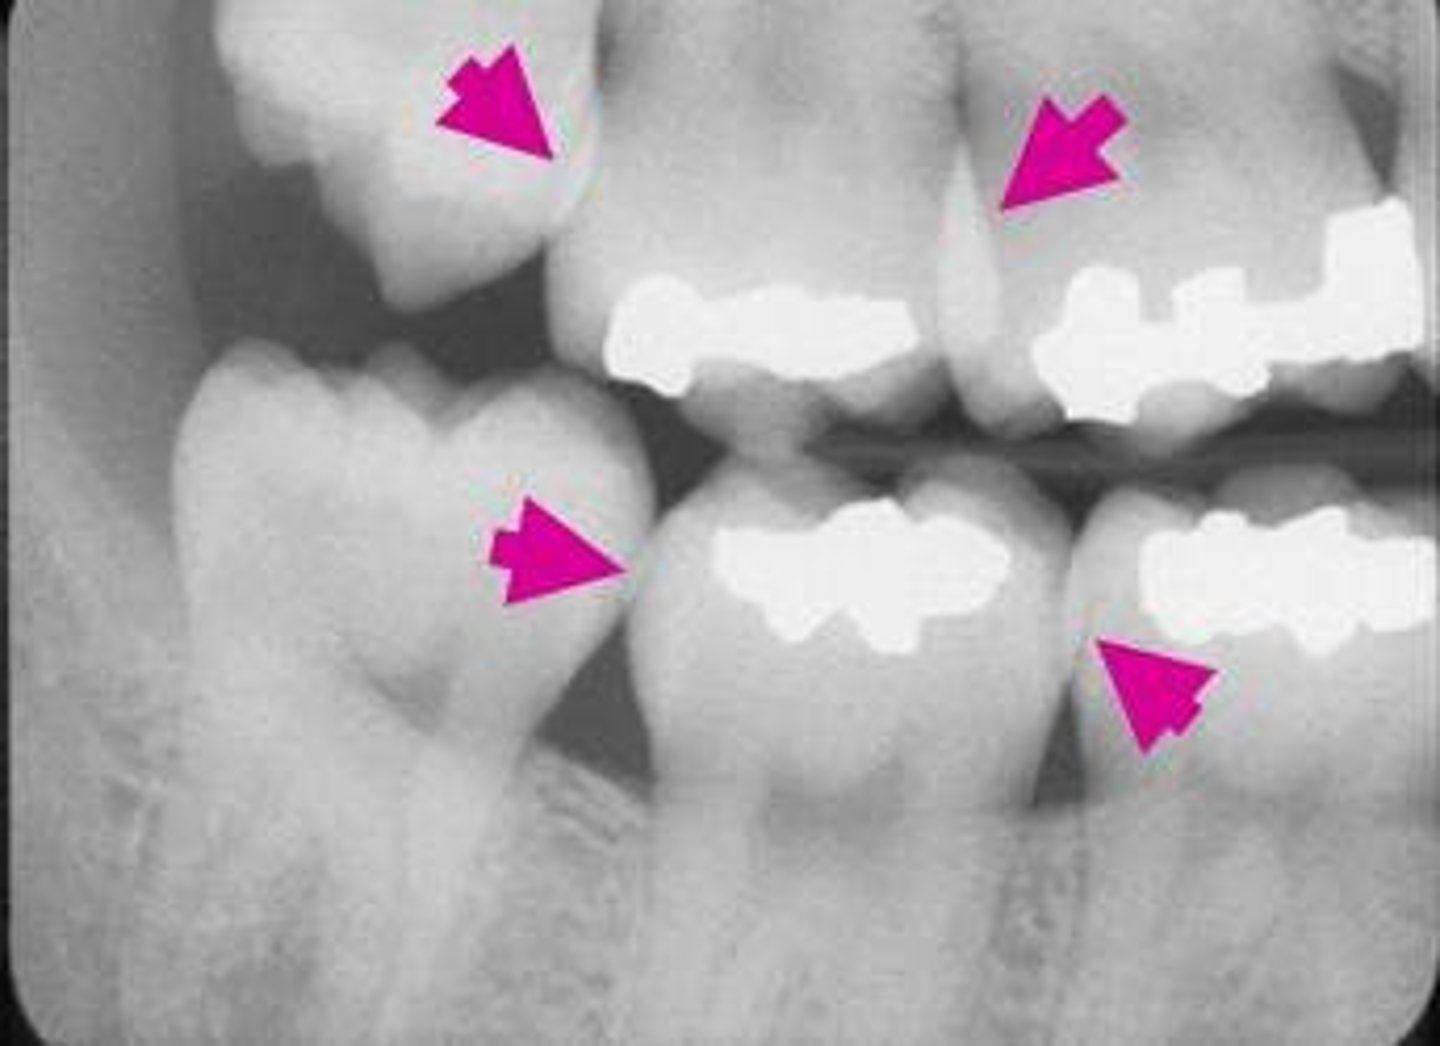

Overlapping